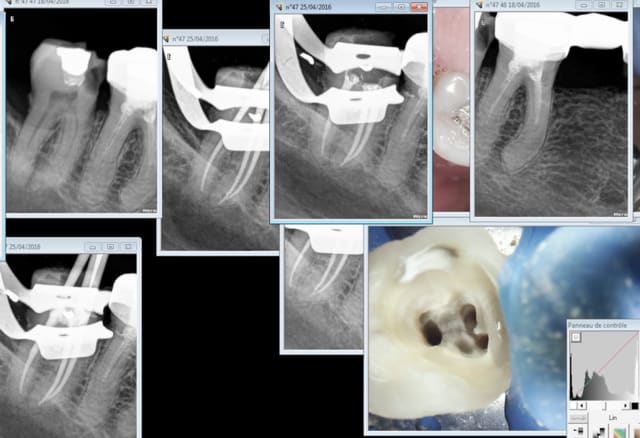

Tiens cas pratique. A ton avis c'est moi qui ait fait l'endo sur 46 ? -)

Ce genre de traitement c'est tous les jours que tu en vois. Coup de bol pas de peche.

Bien sur celui qui a fait ca réussit sa pratique en endo à la fac tu lui mets 20/20 ? -)))

Alors oui ce système encourage la médiocrité. Pour éviter le burn out il faut en avoir rien à secouer.